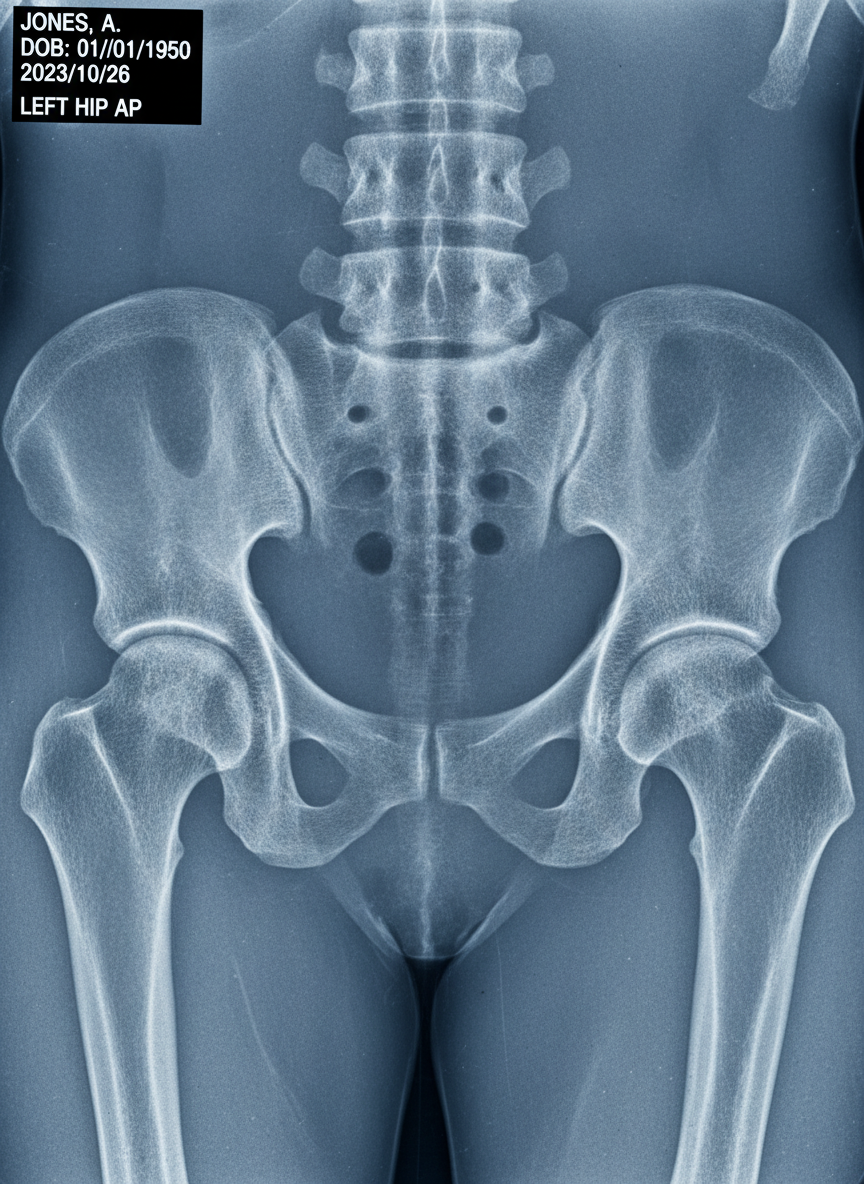

💡 알고 계셨나요? 고관절은 허벅지 뼈의 머리 부분(대퇴골두)과 골반 뼈의 움푹 들어간 부분(비구)이 만나 이루어진 구형 관절이에요. 이 견고하면서도 유연한 구조 덕분에 우리는 다리를 자유롭게 움직일 수 있답니다.

| 사타구니 통증 | 걷거나 다리 들 때, 양반다리 시 악화 | 고관절염, 대퇴골두 무혈성 괴사, 고관절 충돌 증후군 |

이런 증상들은 고관절염, 대퇴골두 무혈성 괴사, 고관절 충돌 증후군 등 다양한 질환의 신호일 수 있기 때문에, 정확한 진단을 통해 적절한 치료를 받는 것이 매우 중요해요. 통증은 우리 몸이 보내는 경고음이라는 사실을 잊지 마세요.